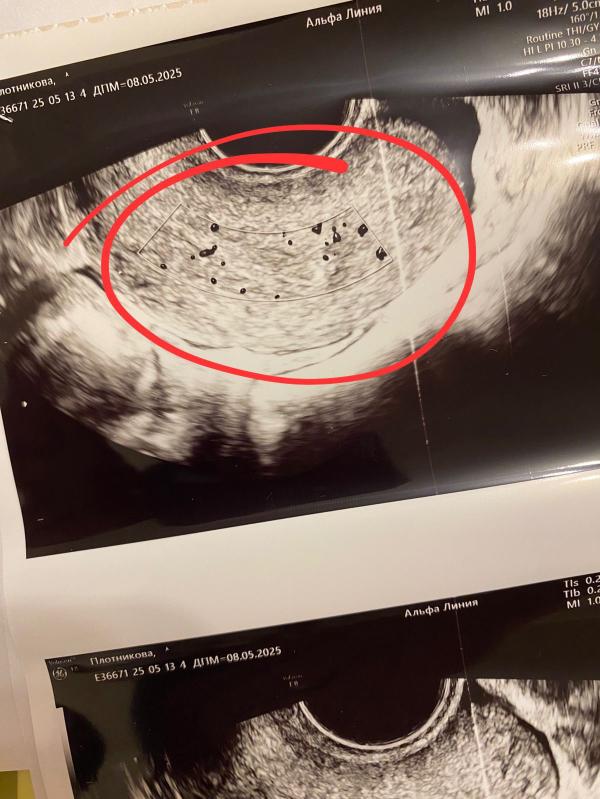

Девушки, привет. Была повторно на узи на 5 день цикла. Всё так же эндометриоз ставят диагноз и предлагают гистероскопию. Прикрепила фото и заключение, у кого нибудь было так по узи? Что это может быть? На экране показывает кровоток. На миому врач сказала не похоже. Помогите разобраться. Целесообразно ли ехать в Краснодар к своему гинекологу? Для консультации что делать дальше и так ли нужна гистероскопия мне, или достаточно мнение данного врача и двух результатов узи? 3 фото это в прошлом месяце